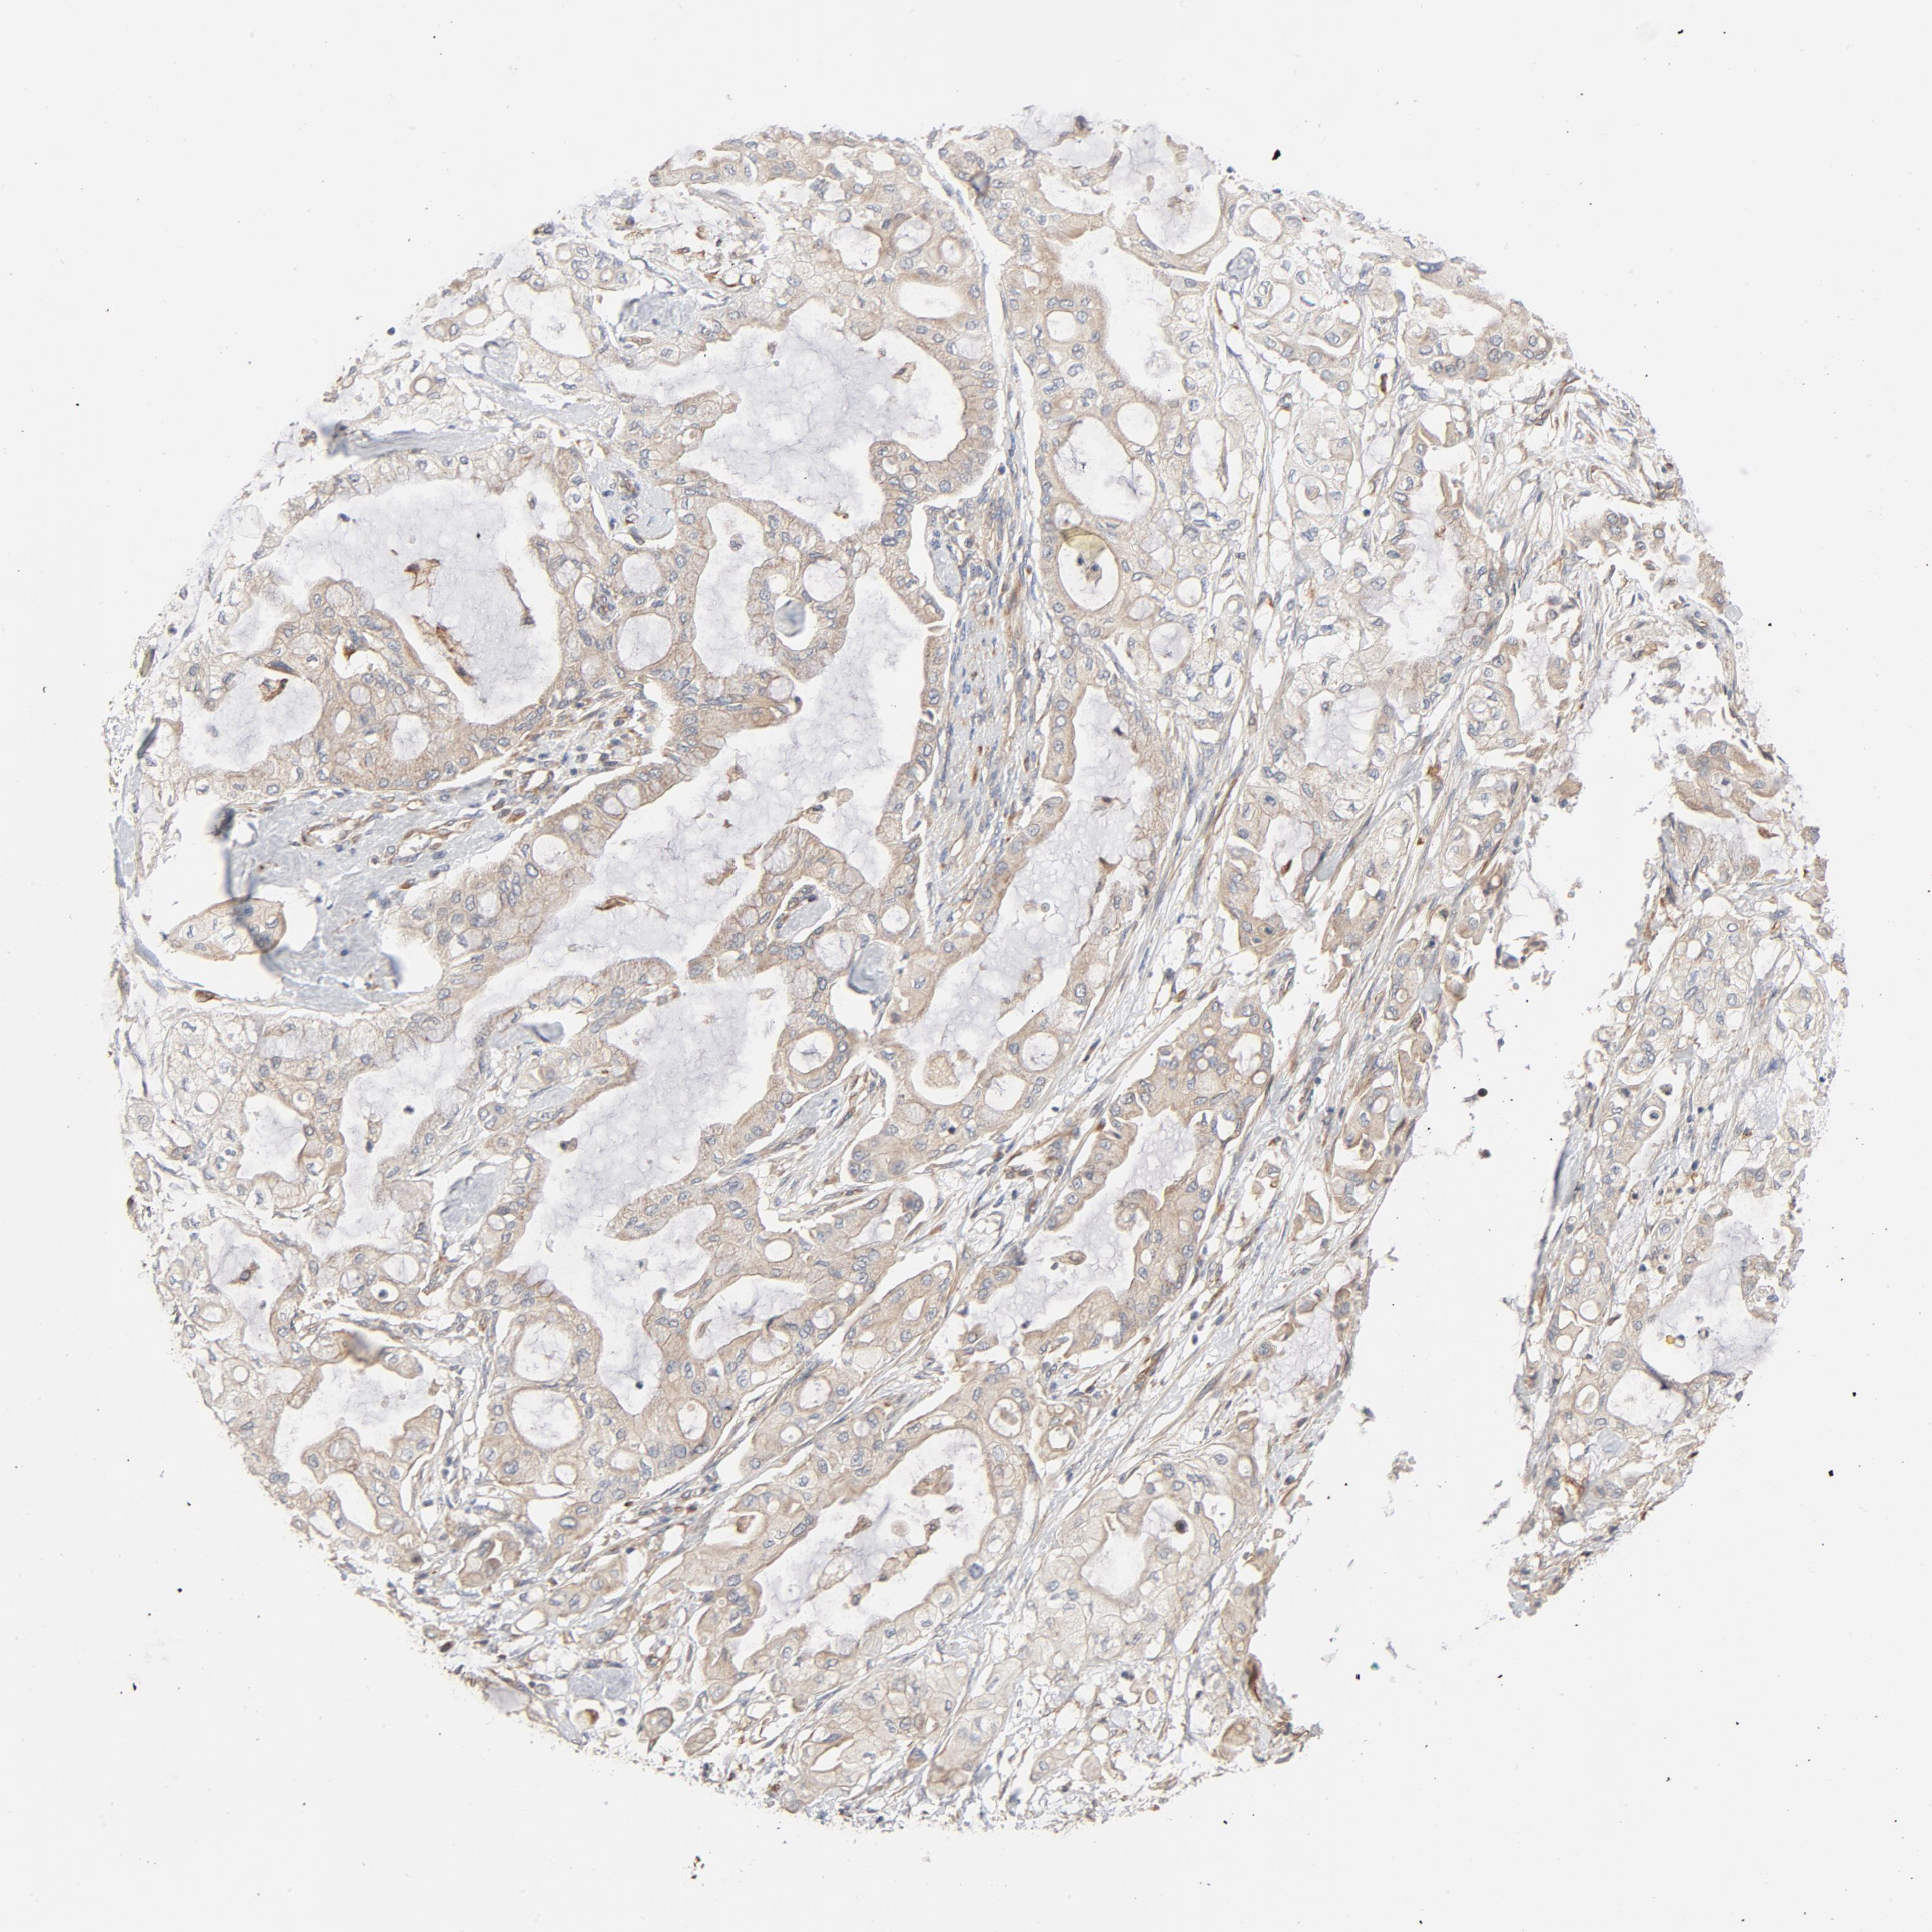

PANCREATIC CANCER - Protein expressioni

A mouse-over function shows sample information and annotation data. Click on an image to view it in a full screen mode. Samples can be filtered based on level of antibody staining by selecting one or several of the following categories: high, medium, low and not detected. The assay and annotation is described here.

Note that samples used for immunohistochemistry by the Human Protein Atlas do not correspond to samples in the TCGA dataset.

Antibody stainingi

Antibody staining in the annotated cell types in the current human tissue is reported as not detected, low, medium, or high, based on conventional immunohistochemistry profiling in selected tissues. This score is based on the combination of the staining intensity and fraction of stained cells.

Each image is clickable and will lead to virtual microscopy that enables deeper exploration of all samples and also displays staining intensity scores, fraction scores and subcellular localization as well as patient and tissue information for each sample.

Antibody HPA003747

Antibody HPA019769

Adenocarcinoma, NOS

Adenocarcinoma, metastatic, NOS